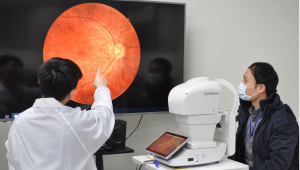

Завдяки автоматичному 3D-відстеженню та фокусуванню зображення сітківки ока можна робити одним дотиком. Функція повної автоматичної зйомки скорочує час обстеження, що не тільки спрощує процес обстеження для лікарів і медсестер, але також зменшує дискомфорт або навантаження для пацієнтів.

Користувачі можуть зберігати, отримувати, архівувати та обмінюватися цифровими зображеннями за допомогою USB-накопичувачів або локальної мережі. NFC-700 також сумісний з DICOM, що полегшує інтеграцію з програмою PACS. Користувачі можуть передавати, роздруковувати або обмінюватися інформацією через Ethernet, HDMI або USB.